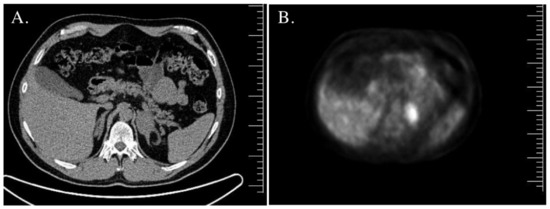

| Adrenal gland imaging | Normal. | CT—bilateral adrenal tumors, right—45 mm × 30 mm × 37 mm (20 HU), left—18 mm × 14 mm × 11 mm (30 HU). | MRI—right adrenal tumor, 85 mm × 57 mm × 70 mm; inhomogeneous, without signal loss in out-of-phase. Left adrenal hypertrophy. | MRI—left adrenal tumor, 44 mm × 38 mm; inhomogeneous, borderline signal loss in out-of-phase; 18FDG PET/CT—increased uptake. Right adrenal in normal size. |

| Adrenal gland imaging | CT—right adrenal tumor 20 mm, 26 HU; MRI—signal loss in out-of-phase. Left adrenal normal in size. | CT—bilateral adrenal hypertrophy. | MRI—left adrenal tumor 44 mm—borderline signal loss in out-of-phase; right adrenal adenoma 16 mm × 10 mm × 7 mm; 18FDG PET/CT—increased uptake (SUVmax 7.6) in the left adrenal tumor. | CT—bilateral adrenal hypertrophy (left adrenal 42 mm × 30 mm, right adrenal 55 mm × 35 mm). |